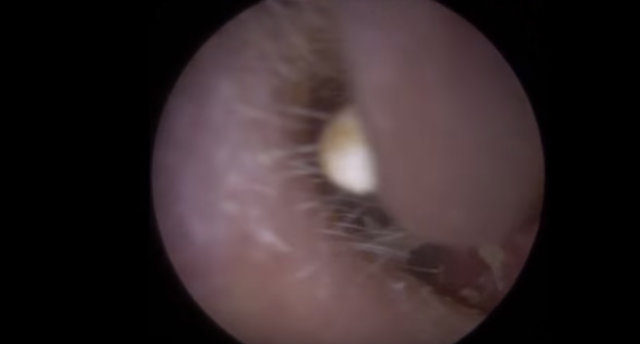

Kulağından 22 tane nesne çıkarılan adam hayrete düşürdü. İşin garip yanı ise kulağının içinden çıkan şeylerin işitme cihazı olmasıydı...